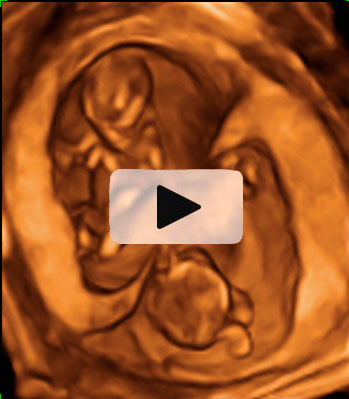

Ecografía 4D de la semana 12: Gemelos contrapeados

Ecografía en 4D de gemelos de 12 semanas "contrapeados" En este caso, el gemelo que "baila" es el que está en parte inferior de la imagen o cabeza abajo.